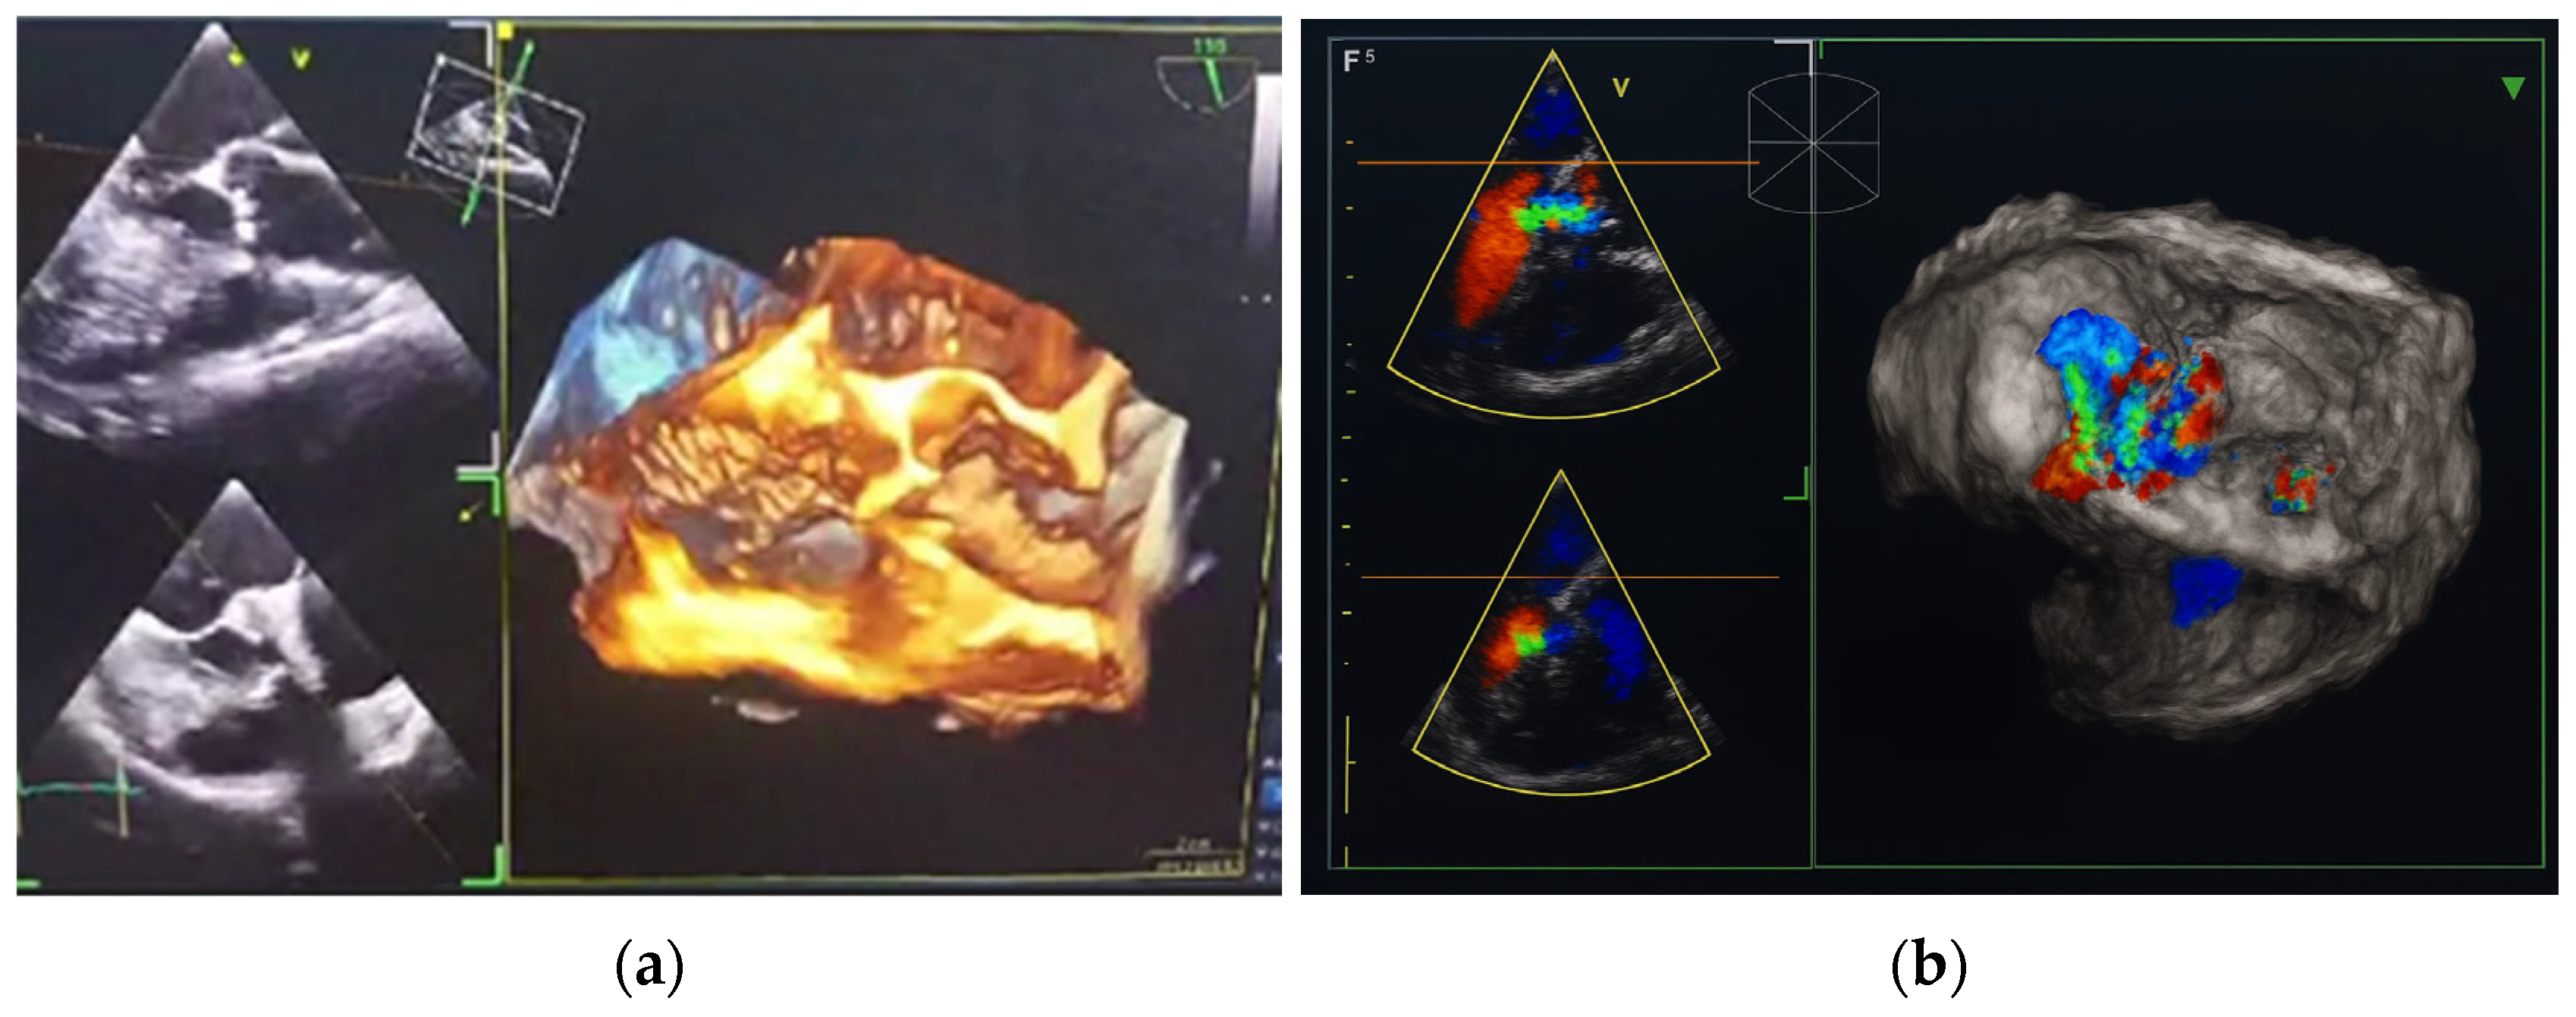

In October 2024, the patient was admitted to our Division of Rheumatology and Immunology due to exacerbation of her underlying overlap syndrome, demonstrating moderate to high disease activity: Disease Activity Score 28-ESR was 4.95 and Systemic Lupus Erythematosus Disease Activity Index was 6. Clinical symptoms included continuous moderate chest discomfort and worsening dyspnea upon exertion. She denied gastrointestinal or respiratory complaints, fever, or systemic signs of infection. Her long-term pharmacotherapy regimen included prednisone 7.5 mg/day, pantoprazole 40 mg/day, atorvastatin 20 mg/day, cholecalciferol 20,000 IU weekly, furosemide 40 mg/day, and lercanidipine 10 mg/day. Vital signs on admission were stable: blood pressure 140/90 mmHg, heart rate 76 bpm, and temperature 36.7 °C. Cardiovascular auscultation revealed a grade 2/6 systolic murmur over the precordium. Musculoskeletal examination was notable for bilateral wrist synovitis, bilateral shoulder pain with restricted range of motion, right knee arthralgia with limited mobility, and fixed flexion deformities of the right-hand fingers and left elbow. There was no clinical evidence of peripheral edema. Laboratory evaluation revealed: leukocytes 6500/µL, hemoglobin 88 g/L, platelets 188,000/µL, C-reactive protein (CRP) 11.7 mg/dL, erythrocyte sedimentation rate (ESR) 50 mm/h, hypocomplementemia (low C3 and C4), serum urea 4.9 mmol/L, and serum creatinine 144 µmol/L. Immunological testing showed negative RF and ACPA. Antinuclear antibodies (ANA) were positive at a titer of 1:160 with a homogeneous nuclear staining (AC-1 pattern). Anti-dsDNA was markedly elevated (86 IU/mL), and antiphospholipid antibodies (aPL), including lupus anticoagulant (LA), were triple positive. All other extractable nuclear antigens tested negative. High-sensitivity troponin I was elevated (84.0 ng/L), whereas N-terminal pro b-type natriuretic peptide (NT-proBNP) remained within normal limits (68.5 ng/L), and ECG findings were unremarkable. Due to persistent anemia, dyspnea, and dysphagia, repeat esophagogastroduodenoscopy was performed, confirming histologically proven erosive Helicobater pylori-negative gastritis. Repeat MSCT coronary angiography again ruled out acute coronary syndromes. Repeat TTE revealed a degenerative bicuspid aortic valve with a rudimentary left coronary cusp and moderate AR (aortic valve area: 2.4 cm2; vena contracta: 4 mm). Transesophageal echocardiography (TEE) confirmed these findings and offered a more detailed evaluation of valvular morphology and the severity of AR (Figure 2 and Figure 3).

Figure 3.

Transesophageal heart ultrasound 3D imaging. (a) 3D reconstruction of the aortic root and ascending aorta. (b) 3D Color Doppler imaging of aortic regurgitation.